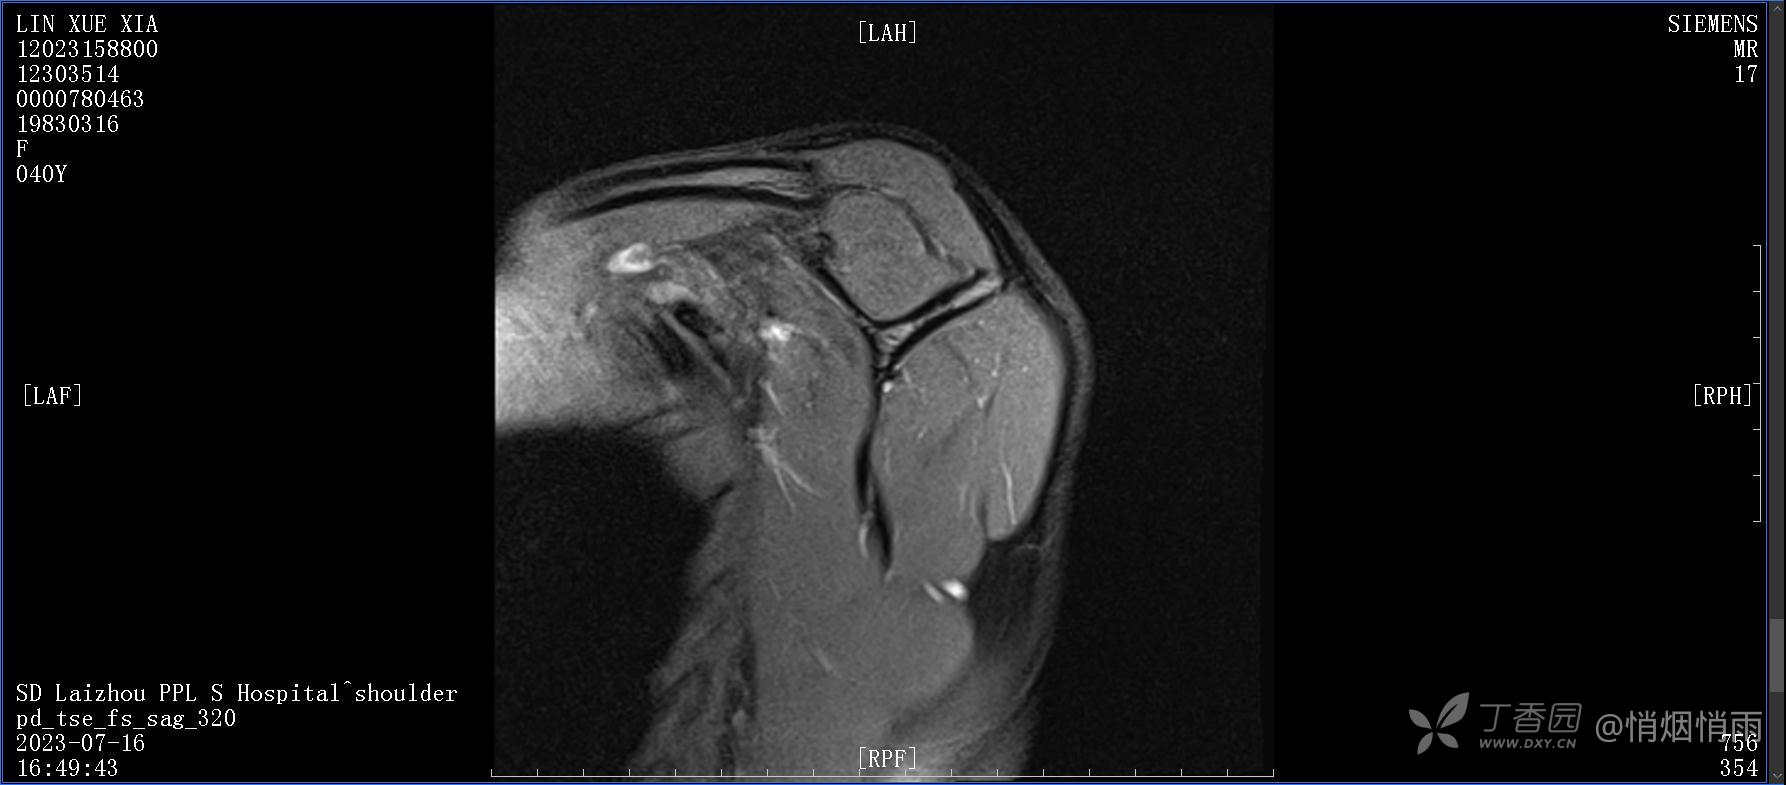

查体:右肩关节局部轻度肿胀,肩胛区压痛明显,痛处不固定,肩关节痛性活动受限,jobe test(+),lift -off test(+),中指、环指感觉较余指减退,余肢端感觉及血运情况可。

目前的诊断,暂时依据辅助检查诊为肩袖损伤,但是患者疼痛的性质和特点,却不是单纯的肩袖损伤所致。考虑过胸廓出口综合征,但是该疾病会出现肩胛区的疼痛吗?(由于考虑到费用的问题,没再进行下一步的检查)带状疱疹会有如此的症状吗?